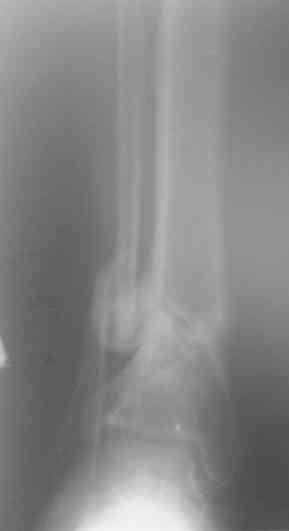

Есть у меня результат такого метода. Тема обсуждалась. Как говорится - лечили всем форумом. Рана, правда, не огнестрельная - OFFтопик.

Больной случайно попал в поле зрения с переломом шейки бедра. Страдает хр. алкоголизмом. От когда-то предложенного удлиннения голени пациент отказался. После снятия аппарата он пропал как с белых яблонь дым ...

Укорочение конечности 3 см. Передвигался без дополнительной опоры с "нарощенной" подошвой на правой обуви. Ограничение тыльного и подошвенного сгибания - умеренные (всего примерно 50%, не измерял).